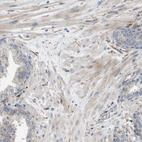

Immunohistochemical staining of human rectum shows strong cytoplasmic positivity in glandular cells.